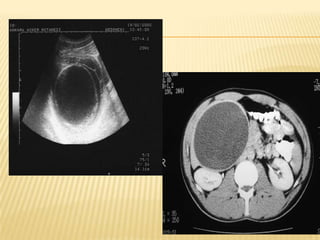

 Huge heterogenous cystic mass in the right liver

lobe measuring > 20.5cm X 12cm.Presence of

gallstone in GB.IHD and CBD not dilated

Imp : suggestive of hydatid cyst with diffrential of

amoebic liver abcess

IMAGING  Usg HBS Huge heterogenous cystic mass in the right liver lobe measuring > 20.5cm X 12cm.Presence of gallstone in GB.IHD and CBD not dilated Imp : suggestive of hydatid cyst with diffrential of amoebic liver abcess *** further history : h/o of multiple visits to egypt within past few years. Last visit was in feb 2013 whr she took local salad dish with grilled fish and snails delicacies